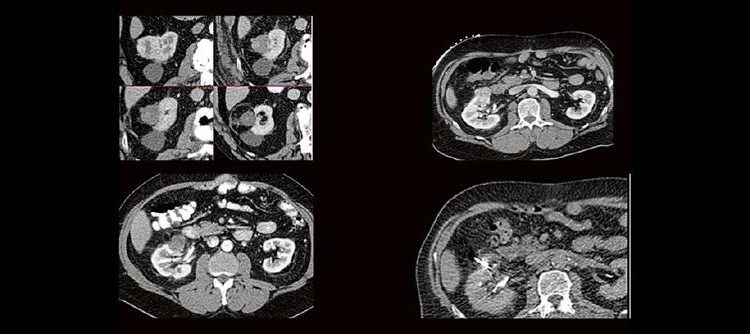

Dr. med. Sascha Alexander Pietruschka Die Anwendung von ablativen Verfahren hat sich in der klinischen Praxis etabliert. Nierentumoren bieten sich für den Einsatz von RFA und Mikrowelle an. Im Dietrich Bonhoeffer Klinikum Neubrandenburg blicken wir auf 15 Jahre Erfahrung mit mehr als 100 RFA/Mikrowellenablationen von Nierentumoren zurück. Im Vortrag werden die eigenen Erfahrungen und Ergebnisse […]